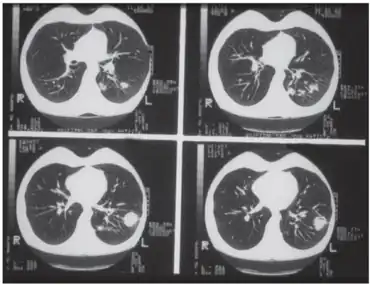

Primary pulmonary histoplasmosis

| Pulmonary histoplasmosis in a 29-year-old female | |

Primary pulmonary histoplasmosis is caused by inhalation of Histoplasma capsulatum spores, and approximately 10% of people with this acute infection develop erythema nodosum.[1]:โ316โ